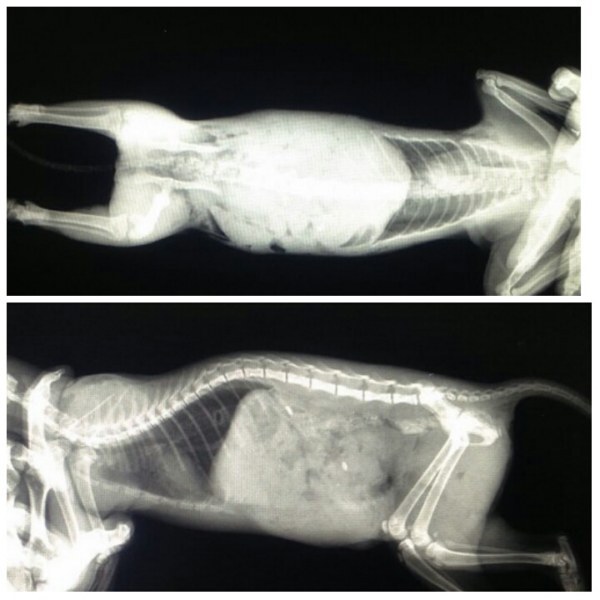

主題: 被狗咬傷與死神拔河但仍去當小天使的福如 申請者姓名: 梁仕宏 花色: 申請日期: 2015-07-21 11:18:06 申請者部落格: 申請者臉書網址: 梁仕宏 所在縣市/合作醫院: 高雄市/弘恩動物醫院 治療費用: 29000元 需求人數: 31人 已結案 (2022-05-13 15:09:04) 報名人員: 何偉靖(已付款)、林小豬 x2(已付款)、Norman Wu(已付款)、ERic YU(已付款)、咪咪貓(已付款)、Alice Tsai x2(已付款)、chun(已付款)、chun、Manman(已付款)、紅色柚子(已付款)、Chen Yu Lin x2(已付款)、lin、Vita Hsiao(已付款)、阿菜(已付款)、nlai1 x2(已付款)、Alisa Huang(已付款)、陳、陳芝榆、Amber Chung(已付款)、Amber Chung(已付款)、fang7880(已付款)、A Jia(已付款)、Choco Chen x2(已付款)、Fatvivian Wang(已付款)、Naiyun Hsu(已付款)、Ed Tsai x2(已付款)、玥青(已付款)、林小儀 x2(已付款)、 候補人員: 動物病情說明: 福如是梓官區的流浪孩子,僅約4~5月大,在7月4號凌晨,被之前在協會留言板要幫大橘結紮的黃小姐發現被狗咬傷,傷勢嚴重,先以電話向我詢問急救事宜,由於高雄地區僅有宏力(通報時誤植為宏仁)及中興兩家設有24小時急診,於是我們決定直接將福如送至宏力醫院進行緊急手術,福如到院時已呈現半休克狀態,無法麻醉,故宏力林醫師不斷輸液維持牠的血壓,並先將被狗咬破的兩側皮膚先行縫合,到早上9點,將福如轉至弘恩醫院繼續搶救。

由於福如失血及感染嚴重,尚不適宜立即開刀,故醫院持續施打抗生素等藥物及輸液,以增加牠的體力及讓身體達到可以接受手術的狀況,在7月4號晚上7點進行腹腔兩側修補手術,右側腹壁被咬破腸子外露,左側腹壁被咬破脾臟破裂失血(手術時已凝結),手術進行時體溫曾降至25度,因感染失血嚴重故有一併輸血,但牠還是撐過手術難關,術後仍給予抗生素及氧氣治療。術後因感染還是嚴重故一直昏睡中,7月6日醫院來電通知福如人需第二次捐血,請我找尋5kg以上之貓咪輸血,因我人在外開會無法處理,於是拜託另位志工林善秋協助po寵物捐血網求援,並先帶我的家貓去捐血救急,所幸家貓與牠血液無互斥反應,故抽取50cc血液輸血,晚上8點時至醫院接家貓並探視,福如尚未完成輸血,但精神也有好轉,體溫也有上升,再持續觀察再決定是否要繼續輸血,期間陸續有中途志工,貓友聯絡可以捐血,在此也要感謝大家的幫忙。7月7日及8日輸血後精神有改善,並有一度自行爬起,但仍未脫離危險。7月9日上午10點突然大量嘔吐休克,醫生盡力急救並施打抗生素緊急輸血仍無法挽回生命而過世。